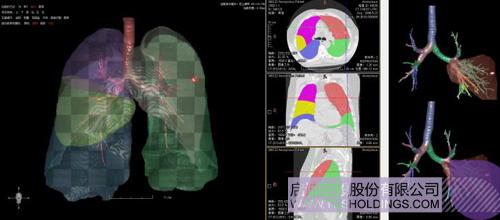

數(shù)字肺產(chǎn)品肺癌計算機輔助診斷

醫(yī)療影像智能分析是指運用人工智能技術、計算機視覺技術以及計算幾何技術對醫(yī)療影像進行自動分析,幫助醫(yī)生定位病癥、分析、跟蹤病情,并通過量化數(shù)據(jù)輔助醫(yī)生做出診斷,目前其旗艦產(chǎn)品“數(shù)字肺”已經(jīng)覆蓋多種肺部疾病的早期檢測、診斷、跟蹤、術前規(guī)劃等完整的醫(yī)療流程。在臨床實踐中,超過80%的醫(yī)療數(shù)據(jù)來自醫(yī)療影像,這些影像數(shù)據(jù)通常需要專業(yè)醫(yī)生進行解讀,工作的重復性高、效率偏低。如果能夠運用智能影像分析技術,同時結合臨床表現(xiàn)以及既往病例進行全面分析,那么就可以大幅度提升影像診斷效率和準確性,讓專業(yè)醫(yī)生的寶貴時間集中在復雜病情的診斷和治療等環(huán)節(jié)。

數(shù)字肺——肺結節(jié)手術規(guī)劃系統(tǒng)